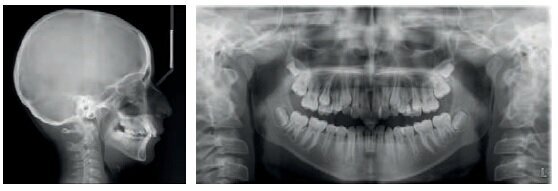

Diagnosis

Class I, incisal-canine crowding in both arches

Class II long face syndrome, hyperdivergent

Retrusive chin

Presence of wisdom teeth buds

A panorex was done to confirm the proper placement of the initial brackets.